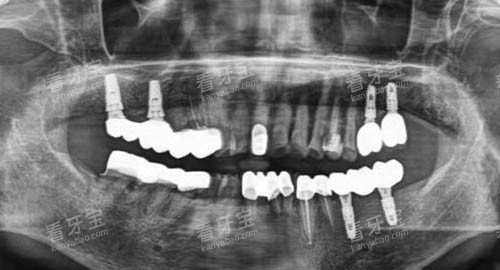

通过口腔 CT 扫描仪,医生可以获取患者口腔的三维影像数据,清晰地了解牙槽骨的密度、高度、宽度等情况,从而精密地确定种植体的植入位置、角度和深度。

通过智能化种植导板的辅助,医生可以在手术前模拟种植过程,更好规划种植体的位置和方向,手术中按照导板的指引进行操作,大大提高了种植手术的精度和效率。